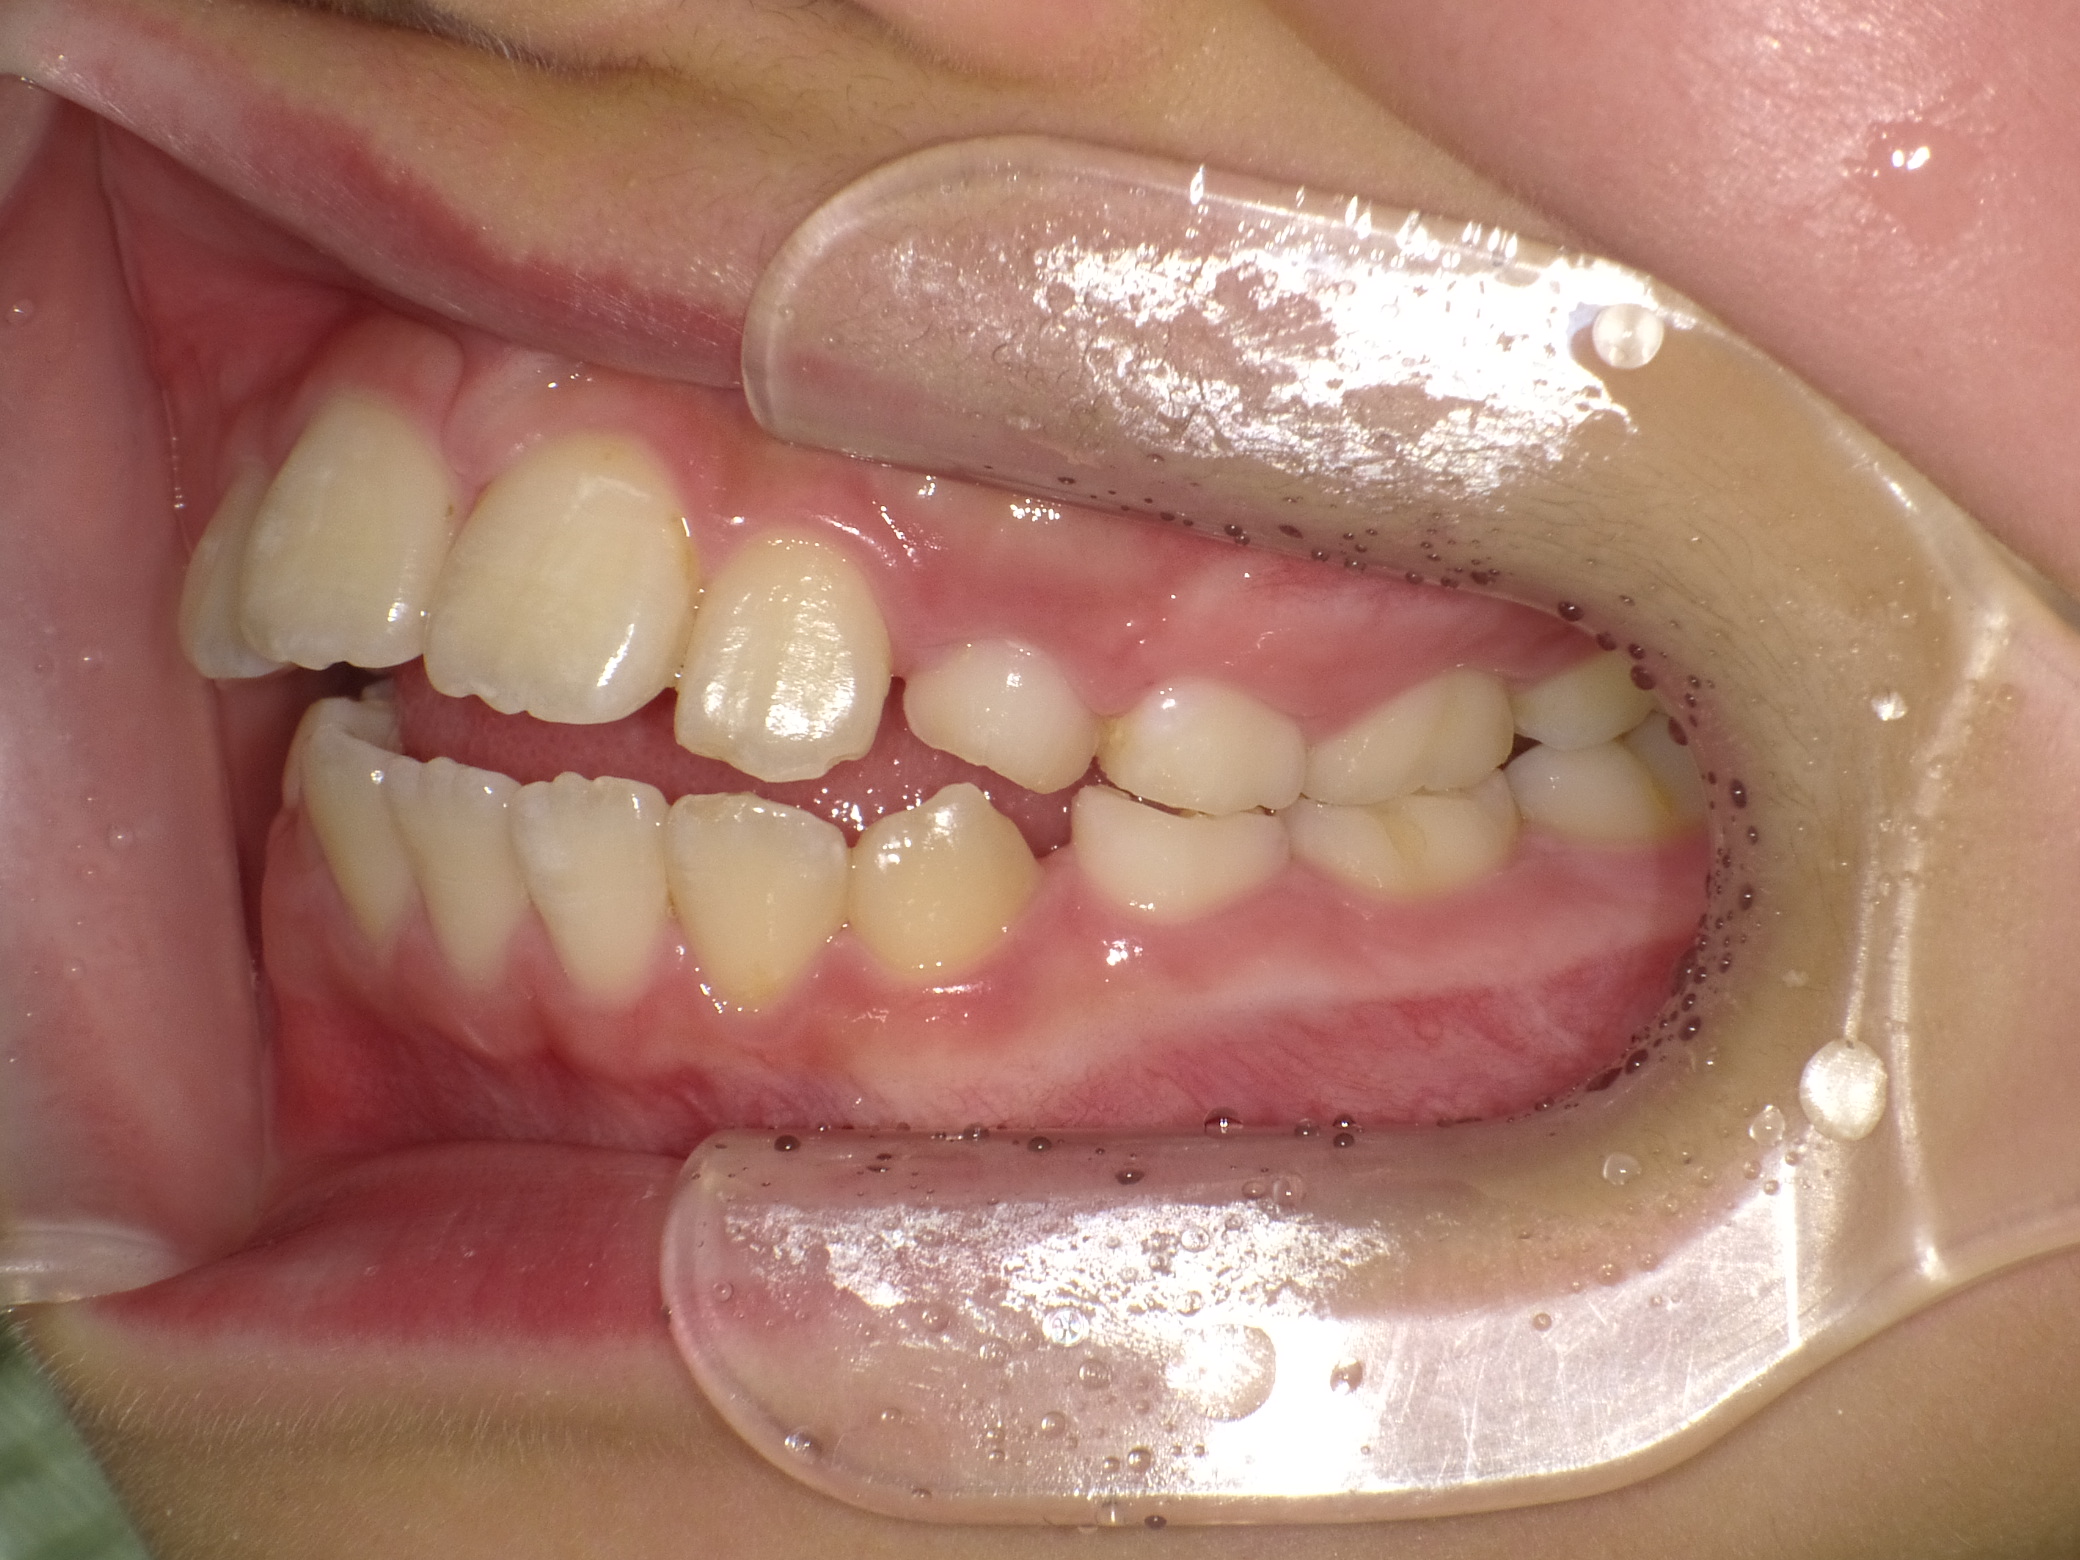

【小学生】マイオブレース矯正 開咬を改善

小学生で開始

マイオブレース

出っ歯

開咬

非抜歯

1期治療のみで改善

Before

After

治療期間

2年

治療開始

8歳

種類

マイオブレース矯正

使用装置

コメント

マイオブレースと 口腔筋機能療法で 咬み合わせが改善しました。

その後 装置を何も付けていませんが 後戻りしていません。

舌癖がある場合、後戻りしやすいですが、

口腔筋機能療法をきっちり取り組んでくれたので

リテーナーなど何も使用せずに安定しています。(AFTERの写真は5年後)